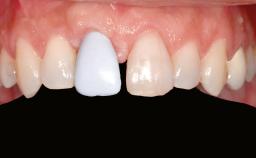

A 45-year-old woman with a completely edentulous maxilla was referred to evaluate the possibility of rehabilitation with an implant-supported prosthesis. This patient was healthy and a non-smoker. She had been wearing a maxillary complete denture opposing a natural mandibular dentition since her twenties. This situation had resulted in progressive resorption of the alveolar ridge, repeatedly creating a need for relining the denture. Twenty years later, despite multiple adaptations and the use of “glues” the denture was unstable and causing the patient psychological and functional discomfort.

Prosthesis Type FDP

Defining Characteristics Fully edentulous upper jaw to be rehabilitated with an implant-borne fixed dental prosthesis

Retention Screw-retained, with 4 or more splinted implants Screw-retained, with 4 or more splinted implants